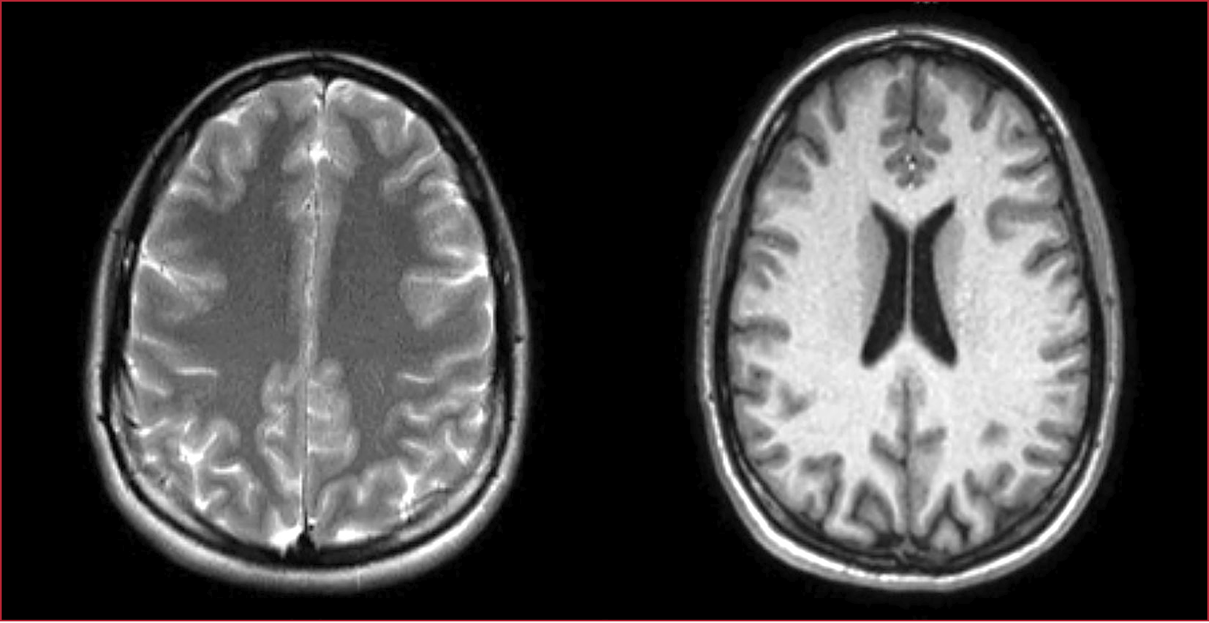

cerebro es normal. Se realiza una PL (Tabla 1). La RM de cerebro no muestra

alteraciones (Figura 1). En el electroencefalograma, no se observa actividad

Figura 1. Caso 1. Resonancia magnética de cerebro. Sin anomalías.